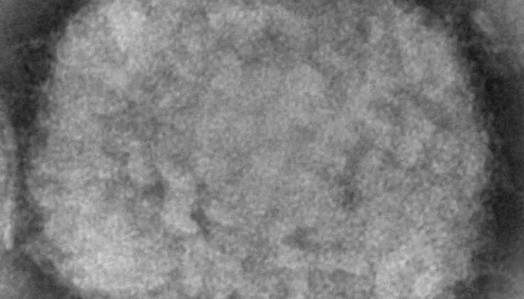

Maymun çiçek virüsü yeni salgına davetiye çıkardı! Avrupa’da vaka sayısı artışta, tedavisi yok

Oldukça ender rastlanan virüs, aniden tüm dünyada tehdit haline geldi. Koronavirüs tam bitecek derken bu virüsün küresel bir salgına dönüşmesi ilgili gelen bilgiler büyük korkuya sebep oldu. Avrupa ve ABD'den peş peşe enfeksiyon haberleri gelmeye başladı.

Başta Avrupa, şimdi de ABD'den gelen tüyler ürperten haberlerle beraber kan donduran gerçek gün yüzüne çıktı. Yeni bir küresel salgın dünyayı risk altına aldı. Son derece ender rastlanan maymun çiçek virüsüne ilişkin dünyanın dört bir yanından gelen haberler oldukça panik yarattı.